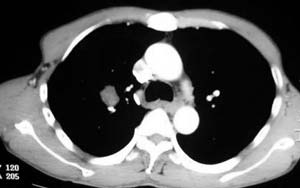

患者,男,58岁,煤矿职工,无症状,单位体检发现病变。

肺窗显示结节的后外边缘呈分叶状生长系生长过程受血管阻挡所致,出现较典型的“树凹”征,部分边缘见毛糙,不均匀强化,楼主未提供增强前后ct值,不好比较,倾向周围型ca。

右肺门上缘见类圆形节结影,密度尚均,边缘清楚,其内可见点状钙化影,周围支气管受压移位,病灶未见明显强化。考虑:1炎性假瘤  2 支持周围型肺ca (腺瘤)

右肺门上缘见类圆形节结影,密度尚均,边缘清楚,其内可见点状钙化影,周围支气管受压移位,病灶未见明显强化。考虑:良性病变——结核球可能性大,周围型肺癌待排。

病灶边缘光滑,似可见分叶征,未见明显毛刺。气管影轻度向右偏移。内可见点样钙化。邻近气道影通畅,考虑结核球可能。请楼主尽快公布结果

右肺门上缘见类圆形结节影,密度尚均,边缘清楚,其内可见点状钙化影,周围支气管受压移位,病灶未见明显强化。考虑:良性病变;首先考虑肺内错构瘤。次考虑肺内腺瘤。

病灶呈分叶型,边缘清晰,无毛刺,增强强化不明显,内见多发钙化,亦无卫星灶。多考虑良性病变。错构瘤可能性大。

病灶呈分叶型,边缘清晰,无毛刺,增强强化不明显,内见多发钙化,亦无卫星灶。多考虑良性病变。错构瘤可能性大或结核球。肺癌待排

动脉相上,右上肺动脉的尖段分支位于结节旁,结节对血管形成压迫而使到走行略改变,并没有很明确的包绕,也没有动脉期的供血,考虑还是偏向于良性可能大。当然最后的决定还是病检

病变边界清晰,对周围主要是外压性改变,未见血管包绕,边缘及中心见钙化,考虑良性病变,结核球可能